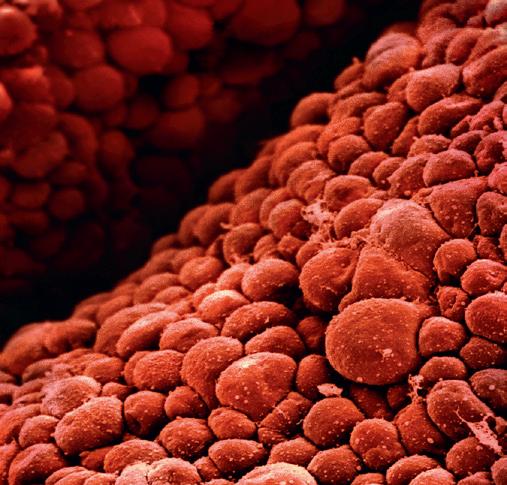

Embryot är knappt mer än en cellklump när hjärtat börjar anläggas, och redan på den tjugoandra dagen i embryots liv drar de nybildade hjärtmuskelcellerna ihop sig och hjärtat slår sina allra första slag. Hjärtats uppgift är central för embryots utveckling: via blodets ständiga kretslopp i blodbanan distribueras näring och syre till alla tillväxande organ.

Så här tidigt i utvecklingen ser hjärtat tudelat ut, och det är så stort och dominerande att det nästan ger intryck av att ligga utanför den övriga kroppen. Högerkammaren tar emot blodet från kroppens organ och vänsterkammaren skickar ut syrerikt blod till kroppens olika delar. Mellan kamrarna sker syresättningen inte som senare i livet via lungorna utan genom moderkakan. I moderkakans kärlträd är motståndet mindre och blodet behöver inte färdas lika långt som i lungorna, så här tas inte så mycket av hjärtats muskelkraft i anspråk.

Hjärtrytmen är mycket snabb, nästan dubbla hastigheten jämfört med den blivande mammans, och den kan lätt fångas upp av en enkel avlyssningsapparat. Att lyssna på hjärtslagens frekvens och rytm är mycket viktigt under graviditeten och ända fram till förlossningen. Hjärtrytmen är en av våra säkraste värdemätare på hur barnet mår i livmodern.